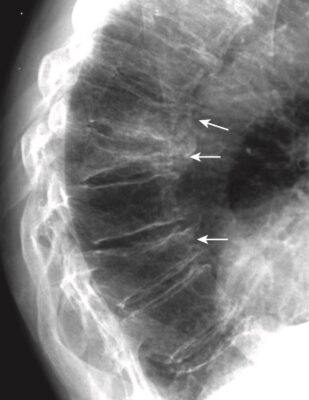

Gãy đốt sống do nén (gãy xẹp đốt sống)

- Các gãy do nén đốt sống thường gặp, ảnh hưởng đến nữ nhiều hơn nam, và thường là thứ phát sau loãng xương. Chúng có thể không có triệu chứng hoặc có thể gây đau ở vùng giữa ngực hoặc vùng thắt lưng trên và thường hết đau sau 4 đến 6 tuần. Đôi khi chúng được phát hiện lần đầu tiên vì thấy gù nhiều hơn, hoặc giảm chiều cao chung của cơ thể.

- X quang cột sống thường quy thường là thăm dò chẩn đoán hình ảnh được lựa chọn đầu tiên. MRI có thể được sử dụng để phân biệt gãy xẹp do loãng xương với bệnh lý ác tính. MRI và quét xương hạt nhân có thể giúp xác định thời gian gãy do nén, điều mà X quang thường quy không thực hiện được.

- Gãy xẹp do loãng xương thường ảnh hưởng đến các mặt trước và mặt trên của thân đốt sống mà không ảnh hưởng đến phần thân sau. Thường có sự chênh lệch chiều cao giữa mặt trước và mặt sau của cùng một thân đốt sống quá 3 mm. Hoặc là, phần thân bị xẹp thường ngắn hơn> 20% so với thân đốt sống trên hoặc dưới.

- Kiểu gãy do nén này tạo ra một biến dạng hình nêm (hoặc chêm, wedge-shaped) làm nổi rõ đường cong gù của cột sống ngực (còn được gọi là bướu của bà goá, dowager’s hump) và làm tăng độ ưỡn ở cột sống thắt lưng (Hình 10).

- Gãy xẹp đốt sống do loãng xương thường không có triệu chứng thần kinh kèm theo vì vết gãy chỉ ảnh hưởng đến phần trước của thân đốt sống, cách xa tủy sống.